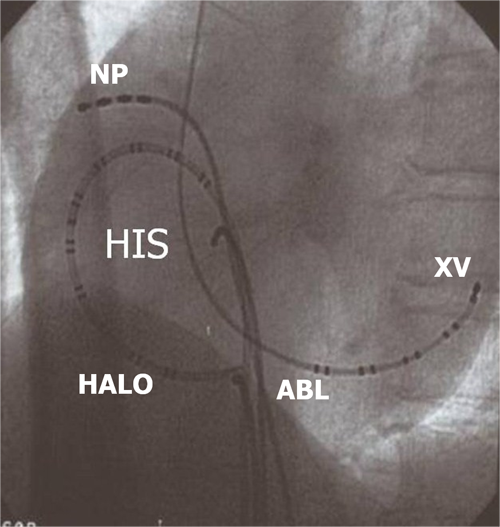

Hình 13: Vị trí các ống thông trên hình ảnh X quang trong triệt đốt cuồng nhĩ điển hình: NP: điện cực cùng cao nhĩ phải, His: điện cực vị trí bó His, XV: điện cực xoang vành, HALO: điện cực trong buồng nhĩ với nhiều cặp điện cực, Abl: điện cực triệt đốt được đưa vào vùng eo van ba lá (ishmus) nằm ở vùng đáy nhĩ phải.